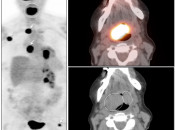

- Maximum Intensity Projection (MIP)

- Fusion of Images